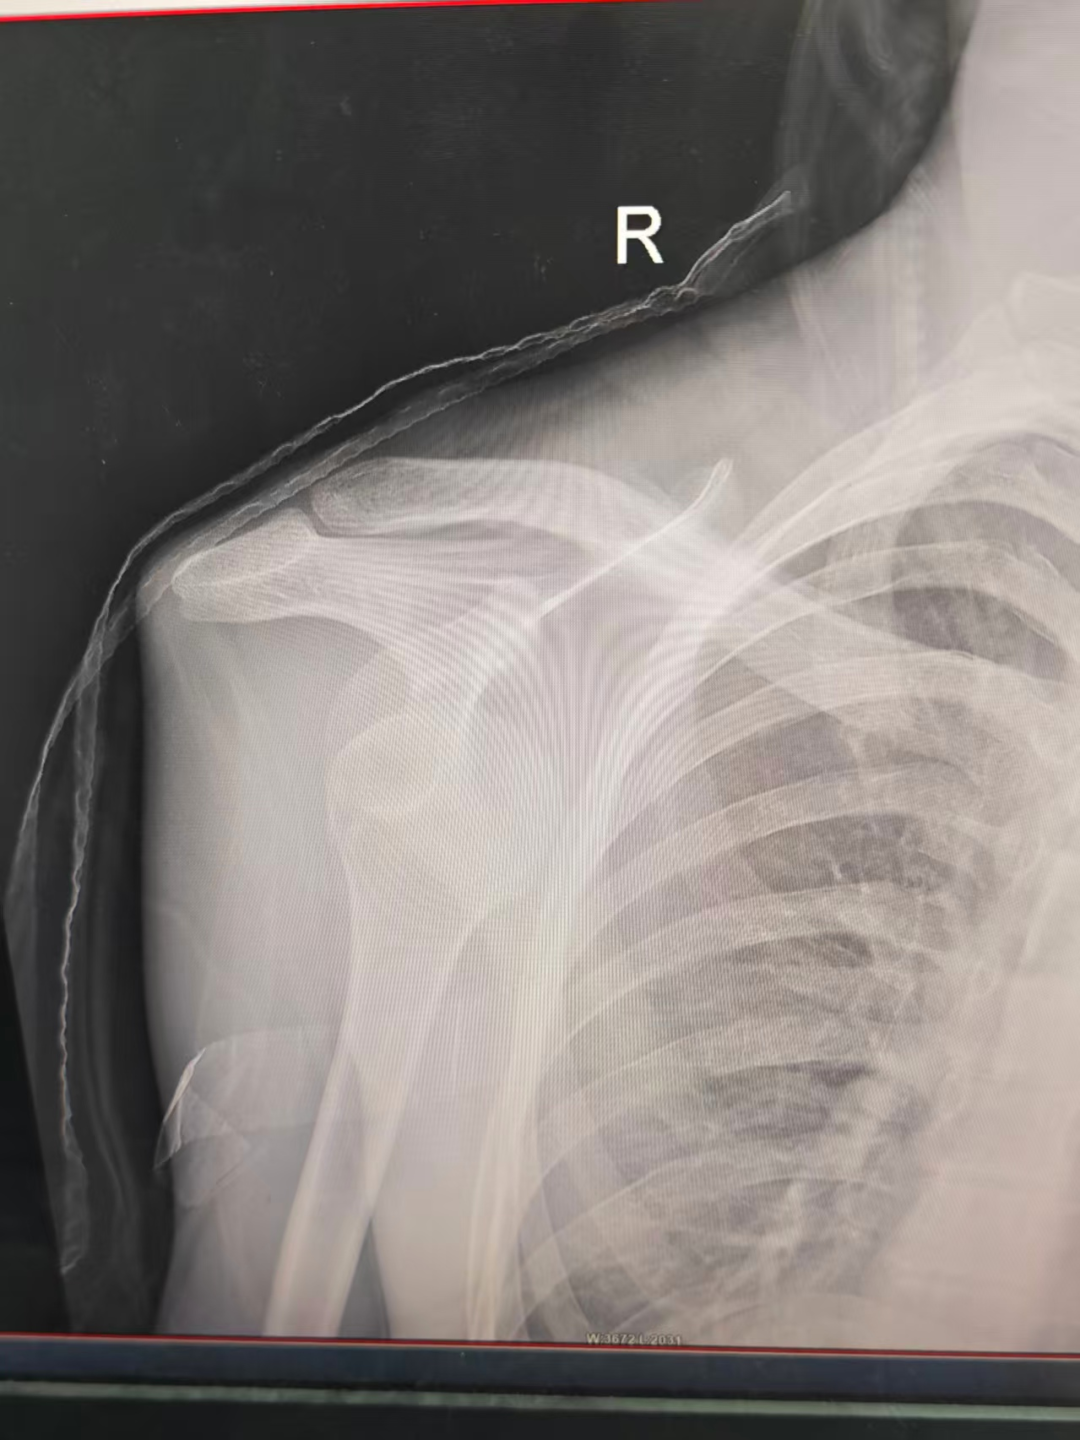

当日白雪宝医生在急诊外科门诊值班,面对这位因运动受伤的中学生,白医生立即接诊,通过详细询问病史和仔细查体,结合患者曾有右肩关节脱位的既往史,迅速判断其很可能再次发生了肩关节脱位。为明确脱位方向和排除骨折,白医生当即为其安排了右肩关节DR检查。检查结果很快证实了诊断:右肩关节前脱位,无骨折。